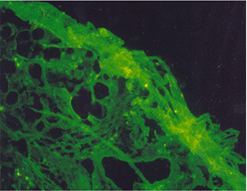

임상증상4

사진32 사진33 사진34

설명32 설명33 설명34